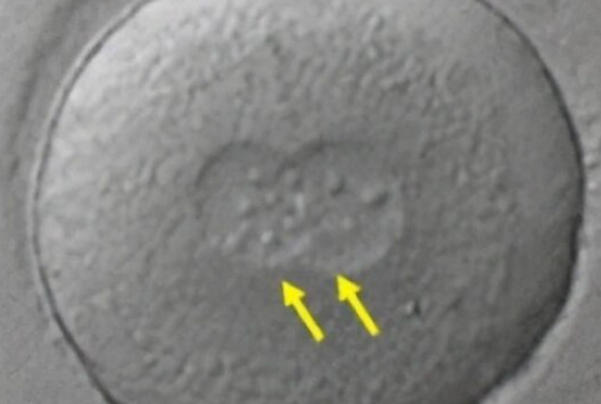

为什么移植1个胚胎却怀上双胞胎?揭秘试管婴儿中的意外惊喜

在试管婴儿治疗中,尽管医生仅移植了一个胚胎,但最终出现双胞胎的情况并不罕见。这种现象的核心原因在于胚胎的“自我分裂”,即单卵双胎的形成。当一枚受精卵在发育早期(通常为受精后3-8天)自然分裂成两个独立的胚胎时,这两个胚胎会携带完全相同的遗传信息,最终发育成同卵双胞胎。研究数据显示,试管婴儿技术中胚胎分裂的概率略高于自然妊娠,可能与其体外培养环境或胚胎操作过程有关。值得注意的是,胚胎分裂的时机决定了